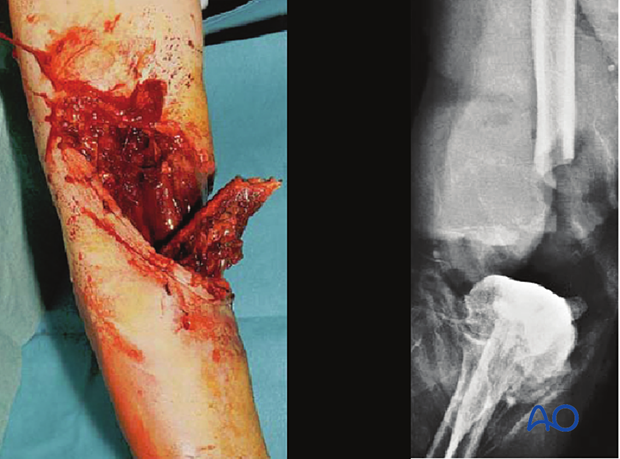

This illustration shows a severe open injury of the shaft of the lower humerus, after a high-energy motor vehicle collision. There was disruption of the brachial artery and vein and neurapraxia of the median, radial, and ulnar nerves. It would be classified as a Gustilo IIIC injury, whereas on the more comprehensive AO/OTA Fracture and Dislocation Classification it would be a 12-C3, IO4-MT4-NV4.